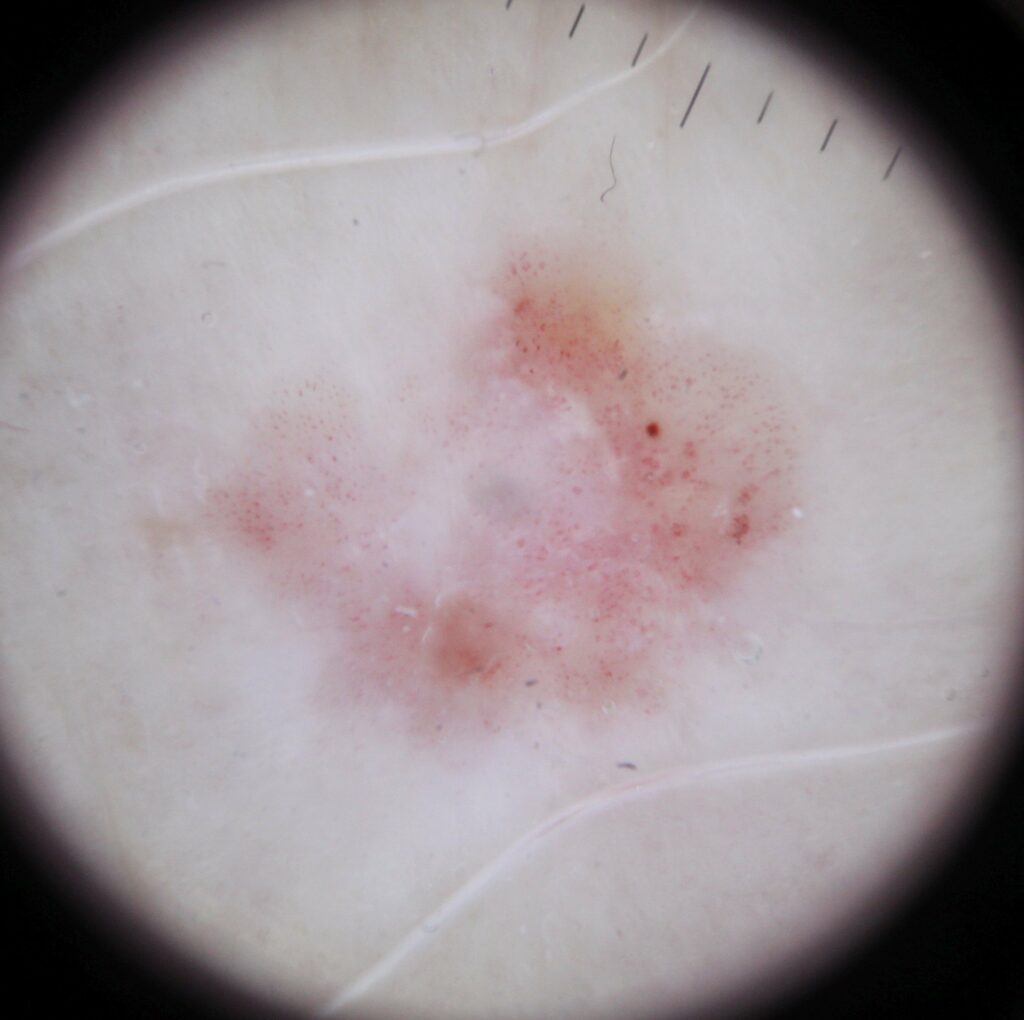

Dermoscopy photo of squamous cell carcinoma in situ (SCCis) skin cancer.

Dermoscopy of squamous cell carcinoma in situ SCCis